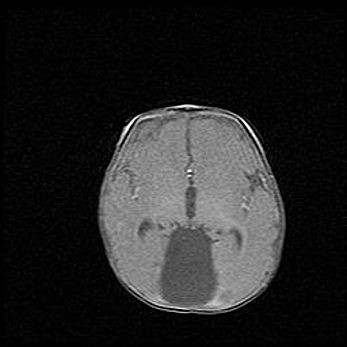

Открытая гидроцефалия.

Возраст: 9 месяцев 12 дней

Вес: 6800 г

Пол: мужской

Окружность головы: 41,5 см

Срок гестации: 28 недель

Гидроцефалия головного мозга у новорожденных имеет характерный признак: опережающий рост окружности головы приводит к визуально хорошо определяемой гидроцефальной форме сильно увеличенного в объёме черепа. Детские неврологи определяют следующие симптомы гидроцефалии у грудничков: выбухающий напряжённый родничок, частое запрокидывание головы, смещение глазных яблок к низу.